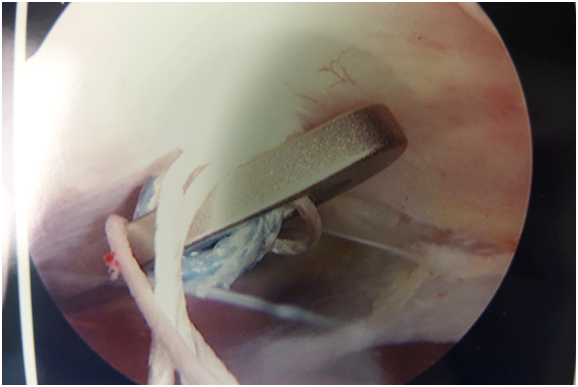

All patients underwent arthoscopic assisted AC joint reconstruction. Patients were placed in the beach-chair position. From the posterior portal, the base of the coracoid was visualized with a 70 degree arthroscope. A vector guide with a guidewire protection stop, inserted through an anterior portal, was placed at the base of the coracoid. A guidewire was inserted through both cortices of the clavicle and the coracoid under arthroscopic visualization. Great care was taken to make certain that the wire was centered anterior-posterior on the clavicle. The wire was placed approximately 2-4 cm medial to the AC joint. The wire was over-drilled with a 4.0 mm drill under arthroscopic visualization. The wire was protected with a curette to prevent advancement during over-drilling. A flexible suture passing wire was placed through the cannulation of the drill. The drill removed and the tightrope pulled into position. The coracoid button was flipped under arthroscopic visualization (Figure 1). The clavicle was reduced manually by a surgical assistant while the top button was fixed into position on the superior surface of the clavicle. It was secured with a minimum of 5 square knots.

Figure 1 Arthroscopic (70 degree) view of flipped button under coracoid.